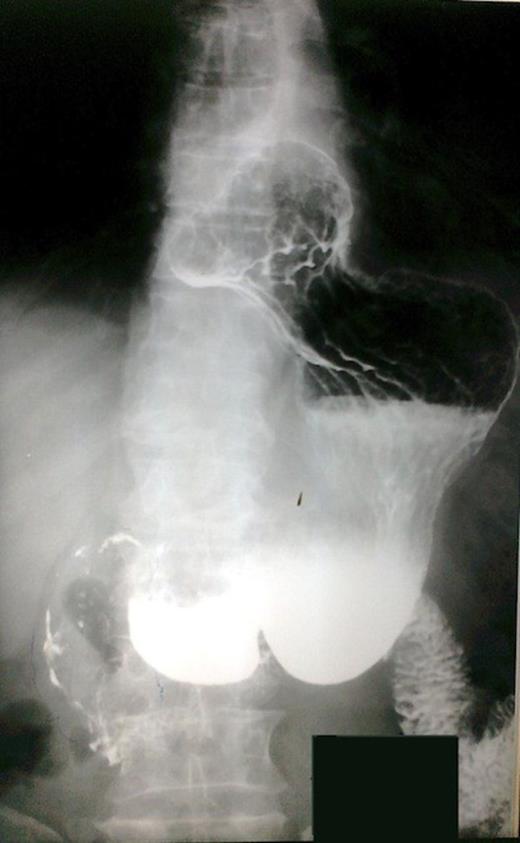

The patient underwent investigation with gastroscopy, where torsion of the bulb of the stomach was found. The insertion of the instrument via the pylorus was not impossible (Figure 1). The upper gastrointestinal series disclosed polypous masses in the bulb and the prepyloric part of the stomach (Figure 2). The computerized tomography (CT) scan was unremarkable. The magnetic resonance (MRI) scan showed an exophytic mass with disturbance of the plication of the intestinal lumen in the area of the pylorus and the duodenum. Also, few small hepatic cysts were found.

Esophagogastroduodenoscopic examination. Prolapsus and torsion of the bulb of the stomach.

Upper gastrointestinal series. Polypous masses in the bulb and the prepyloric part of the stomach